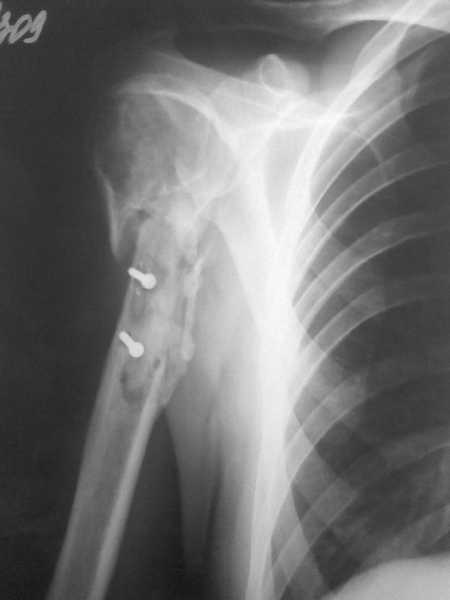

Здравствуйте, коллеги!!! К нам в отделение госпитализирован пациент 39 лет с клинико-рентгенологической картиной ложного сустава в/3 плечевой кости! Снимки прилагаются! Предистория такова: около года назад получил оскольчатый перелом в/3 плечевой кости. В одной из московских больниц выполнен остеосинтез пластиной, через несколько месяцев выполнен реостеосинтез, опять же пластной...., причины реостеосинтеза со слов пациента таковы - "доктору не понравилась как лежит пластина и он ее переложил..." - два месяца назад выполнено удаление фиксатора. Никаких выписок у больного нет. Около недели назад больной ударился областью плечевого сустава, появились боли, в связи с чем он обратился в травмопункт, откуда направлен к нам. Клинически у пациента имеется подвижность в области в\3 плеча, костная крепитация, умеренная болезненность в в/3 плеча при движениях, атрофия дельтовидной мышцы. На следующей недели планируем пациента опериравать. Коллеги, у нас возникло несколько вопросов, если не затруднит, то посоветуйте и подскажите... Мы планируем выполнить закрытый блокируемый остеосинтез, скажите пожалуйста, нужно ли в этом случае, на ваш взгляд, выполнять костную пластику или достаточно выполнить рассверливание костномозгового канала и заштифтовать толстым гвоздем, нужно ли пытаться удалить винты??? У нас в отделении идут дискуссии по этому поводу, придти к общему знаменателю не можем, поэтому и обращаемся к Вам!!! На основании ваших отзывов мы и примем окончательное решение!!! Спасибо!!! Очень ждем Ваших комментариев!!!

1. жизнеспособность головки плечевой кости, которая может быть установлена при КТ плечевого сустава. Если головка нежизнеспособная, то единственной альтернативой артродезу в данном случае является онкологический плечевой протез

2. характер ложного сустава и состояние костных отломков: четкая рентгенологическая картина гипотрофического (аваскулярного) ложного сустава с выраженным склерозом концов отломков и значительным дефектом костной ткани диктует необходимость введения в область ложного сустава остеоиндутивного материала (если бы не было значительного дефекта и склероза концов отломков в межотломковую область можно было бы ввести костную крошку, полученную при рассверливании костномозгового канала). В данном случае значительный дефект кости и плохое состояние концов требует: а)«освежения концов отломков», б) введения в область ложного сустава васкуляризированого костного трансплантатата, либо свободного костного аутоторансплантата, либо выполнение дистракционного остеосинтеза («костного транспорта»). При этом Вам естественно придется «открывать» область перелома, а значит Вы легко удалите винты.

3. состояние костной ткани поврежденного сегмента: в данном случае костная ткань остеопорозна, с многочисленными «дырами» от винтов, ранее фиксировавших пластины. Поэтому фиксировать пластиной третий раза нецелесообразно. Остаются 2 метода: блокированный штифт для проксимального плеча (Т2 страйкер или аналоги), либо аппарат внешней фиксации (чем лучше владеете).

Провести штифт в дистальный отломок закрыто вряд ли удастся: «сосулькообразный» конец отломка, запаянный костномозговой канал, дополнительное препятствие в виде 2 винтов.

В дефекте какие-то признаки жизни вроде есть. Не очень понял, почему головка плеча должна быть в некрозе.

Я бы начал с закрытого удаления винтов и закрытого же штифтования. Канал в периферическом отломке, при неудаче захода в него сверху, можно вскрыть ретроградно. Стержень T2 Stryker - согласен, оптимальный выбор. Действительно, пусть это будет временный эндопротез диафиза. Если за год не образуется ну уж совсем нигде костный мостик, будет сегментарный дефект или явное несращение, можно будет вернуться к этому вопросу, но уже в более благоприятных условиях, чем сейчас.